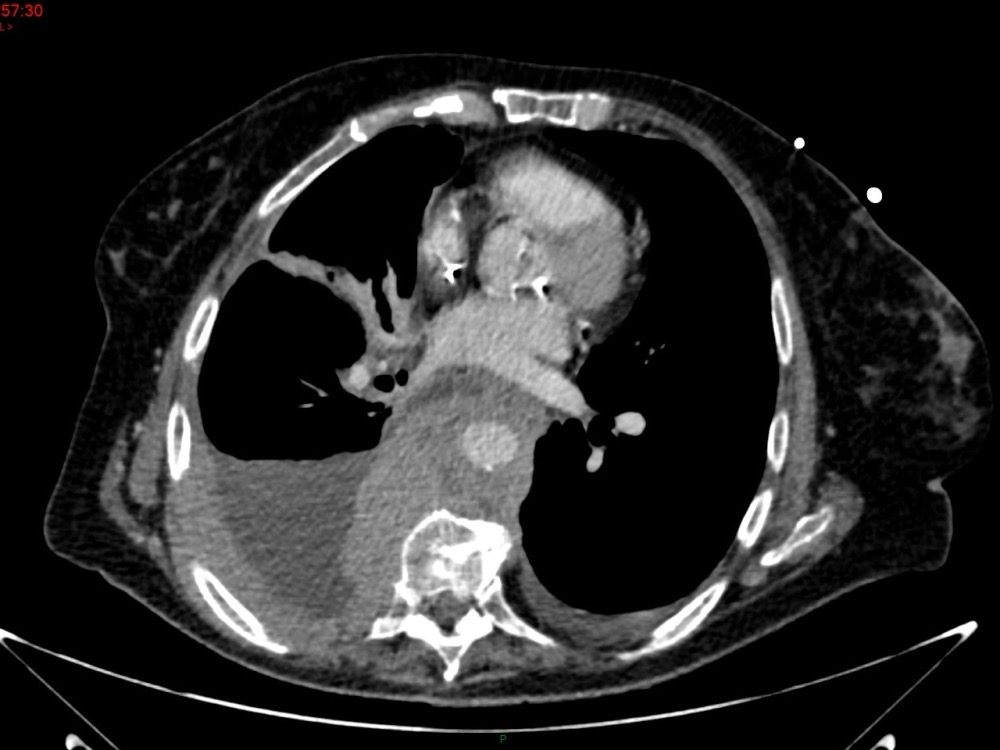

Marie Pauline Talabard 11/01/2023